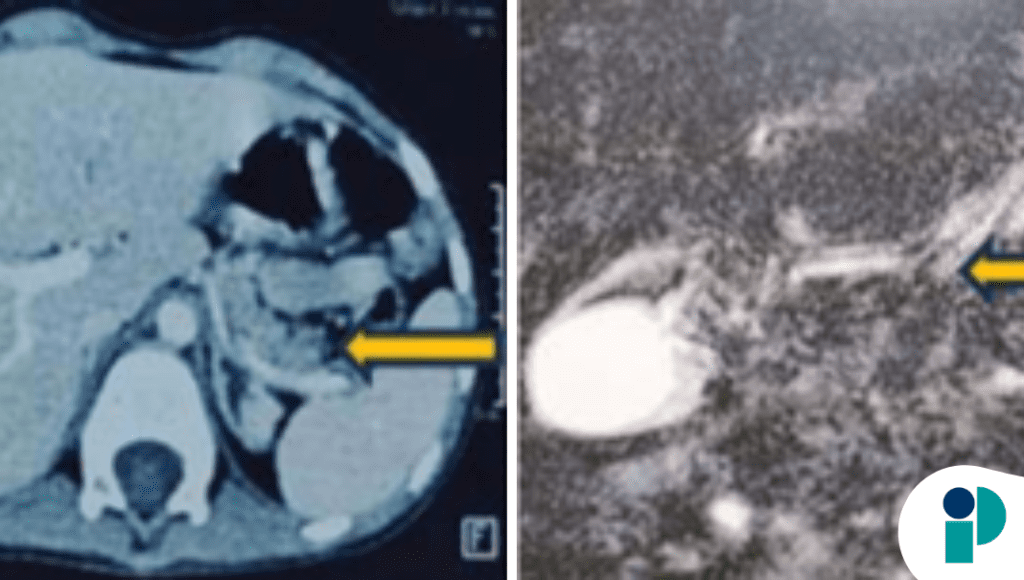

En este paciente, la elevación de amilasa y lipasa, junto con imágenes abdominales compatibles con pancreatitis, puso en evidencia un proceso inflamatorio pancreático. Dada la historia de AIV, los clínicos comprendieron que el metabolismo alterado podía haber desencadenado esta complicación. Se han descrito mecanismos en los que acumulación de metabolitos orgánicos y estrés oxidativo favorecen lesión de células acinares y activación de enzimas pancreáticas, incrementando el riesgo de pancreatitis.